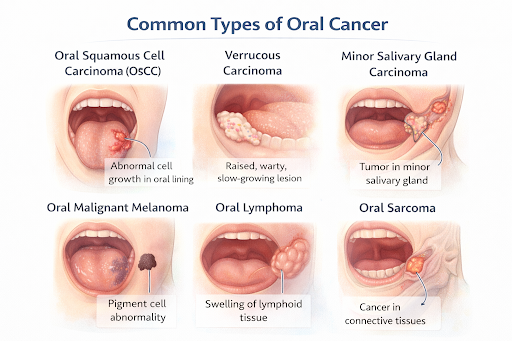

Common Types of Oral Cancer

Oral Squamous Cell Carcinoma (OSCC)

The most common type, originating from the lining cells of the mouth, tongue, lips, and gums.

Verrucous Carcinoma

A low-grade, slow-growing variant of squamous cell carcinoma affecting the oral cavity.

Minor Salivary Gland Carcinoma

Includes cancers like mucoepidermoid carcinoma and adenoid cystic carcinoma arising from small salivary glands in the mouth.

Oral Malignant Melanoma

A rare cancer developing from pigment-producing cells in the oral mucosa.

Oral Lymphoma

Cancer originating from lymphoid tissue within the oral cavity.

Oral Sarcoma

Rare tumors arising from connective tissues such as muscle, bone, or blood vessels in the mouth.

The most common type, originating from the lining cells of the mouth, tongue, lips, and gums.

Verrucous Carcinoma

A low-grade, slow-growing variant of squamous cell carcinoma affecting the oral cavity.

Minor Salivary Gland Carcinoma

Includes cancers like mucoepidermoid carcinoma and adenoid cystic carcinoma arising from small salivary glands in the mouth.

Oral Malignant Melanoma

A rare cancer developing from pigment-producing cells in the oral mucosa.

Oral Lymphoma

Cancer originating from lymphoid tissue within the oral cavity.

Oral Sarcoma

Rare tumors arising from connective tissues such as muscle, bone, or blood vessels in the mouth.